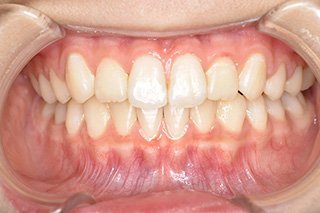

顎顔面矯正症例 11歳女児 Case

| 主訴 | 永久歯が変な所からはえてきている|顔貌 | |

|---|---|---|

| 施術内容 | 矯正1期治療 | |

| 治癒期間 | 1年5ヶ月間 | |

| 費用 | 459,200円(税込) | |

| リスク・ 副作用 | 痛みを伴う | |